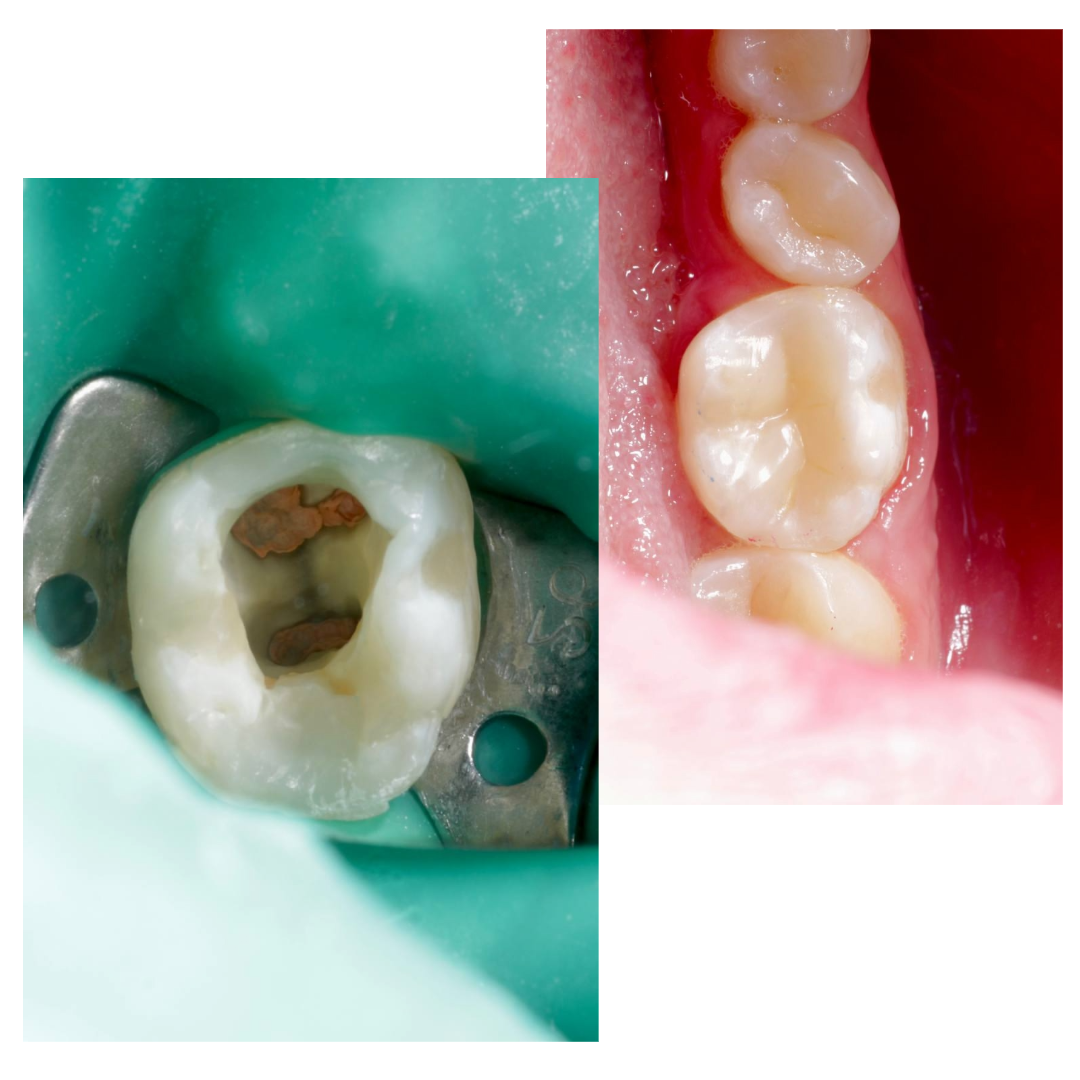

Случай, который демонстрирует, что доставать фрагмент инструмента без увеличения - плохая идея.

Попытки самостоятельно достать фрагмент привели к перерасширению.

Два визита: первый извлечение, второй завершение работы.